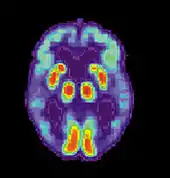

Imaging

Of the many medical imaging techniques available, single photon emission computed tomography (SPECT) appears to be superior in differentiating Alzheimer's disease from other types of dementia, and this has been shown to give a greater level of accuracy compared with mental testing and medical history analysis.[295] Advances have led to the proposal of new diagnostic criteria.[22][121]

PiB PET remains investigational, but a similar PET scanning radiopharmaceutical called florbetapir, containing the longer-lasting radionuclide fluorine-18, is a diagnostic tool in Alzheimer's disease.[296][297]

Amyloid imaging is likely to be used in conjunction with other markers rather than as an alternative.[298] Volumetric MRI can detect changes in the size of brain regions. Measuring those regions that atrophy during the progress of Alzheimer's disease is showing promise as a diagnostic indicator. It may prove less expensive than other imaging methods currently under study.[299]

In 2011, an FDA panel voted unanimously to recommend approval of florbetapir.[300] The imaging agent can help to detect Alzheimer's brain plaques.[301] A negative scan indicates sparse or no plaques, which is not consistent with a diagnosis of AD.[302]